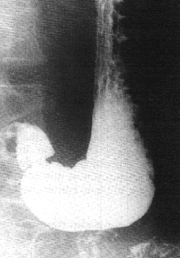

In radiological and experimental anatomical studies of mucosal fold movements Keet (l974, l978) found that normally, transverse or oblique mucosal folds could be demonstrated in the pyloric sphincteric cylinder while the latter was distended or relaxed (Fig. 13.16). (Comment: The terms "transverse" and "oblique" indicate the direction in relation to the long axis. Folds which appear transverse on the two- dimensional radiographic image are in reality circular, surrounding the tube-like lumen. Oblique folds are of a spiral nature).

![]() |

| Fig. 13.16. Pyloric sphincteric cylinder partially distended. All its mucosal folds are transverse (i.e. circular) |

During contraction of the sphincteric cylinder the folds changed in direction, becoming progressively more longitudinal, and with maximum contraction only longitudinal folds were present in the fully contracted pyloric canal (Fig. 13.17). This was a regular occurrence in all our normal cases, including those described here, and appears to be one of the best examples of co-ordinated movements between the muscularis externa and mucosa (muscularis mucosae) occurring in the gastro-intestinal tract.

| Fig. 13.17. Sphincteric cylinder contracted (arrows). The folds have changed in direction to become longitudinal. RPL, right pyloric loop; LPL, left pyloric loop. Note pseudodiverticulum between loops |